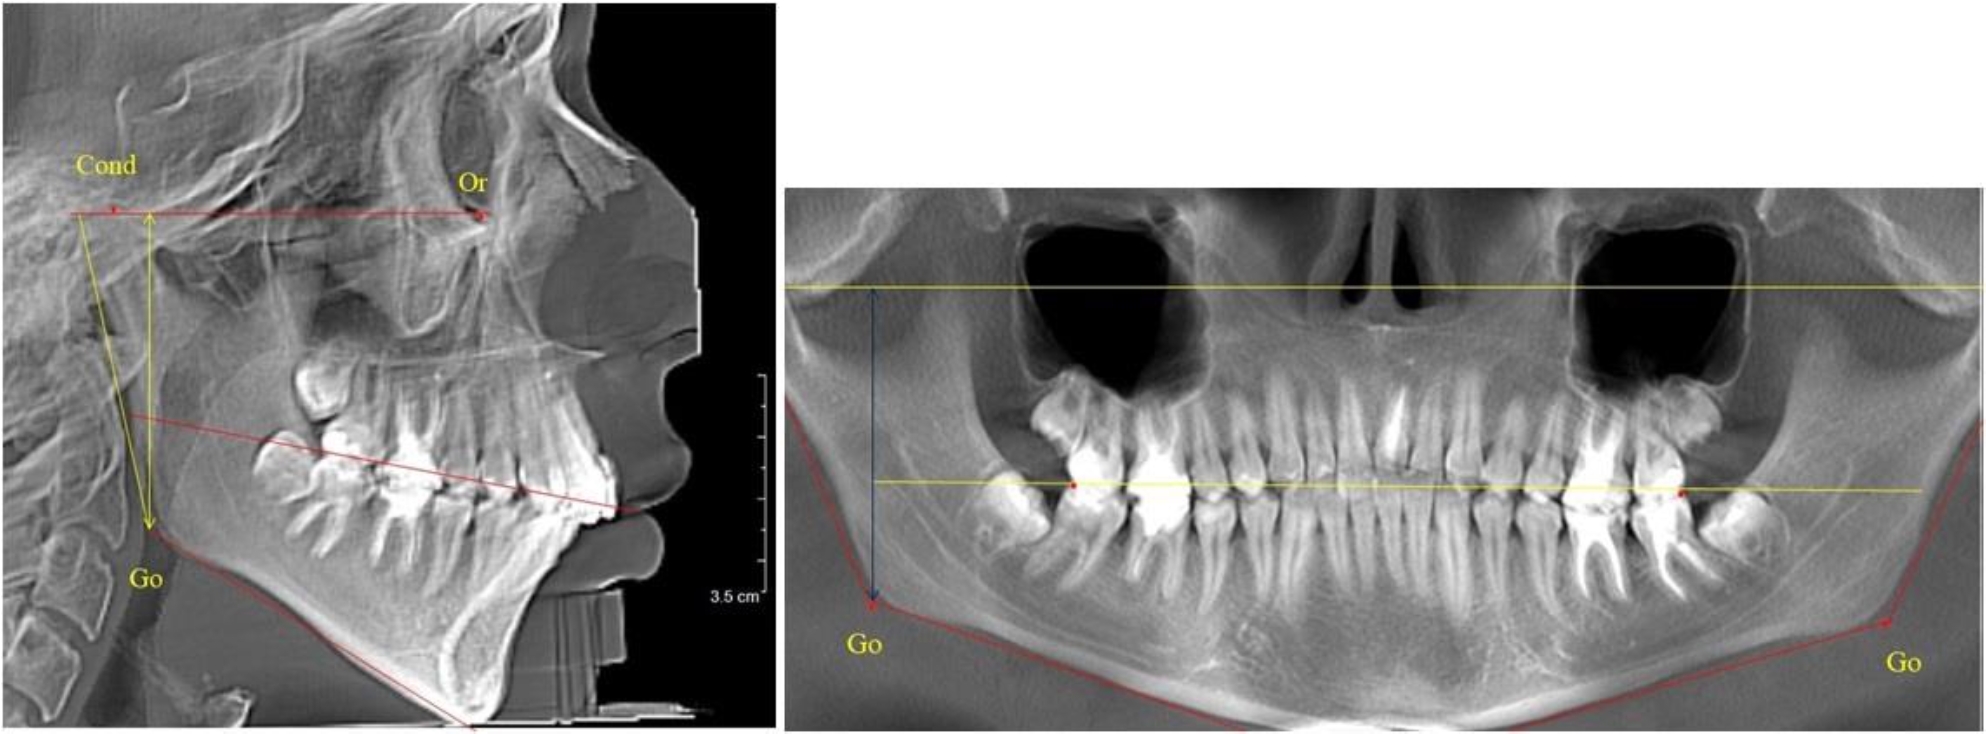

На боковых телерентгенгенограммах вершину суставной головки обозначали точкой кондиион Cond. Касательные линии к ветви и телу нижней челюсти пересекались в точке, которую обозначили Go. Точкой hPOcP обозначали дистальный бугорок нижнего второго моляра вблизи окклюзионного контура коронки. Указанный ориентир соединяли с межрезцовой точкой при построении окклюзионной линии. Высота ветви определялась расстоянием Go-Cond. Окклюзионная линия служила границей между верхней (окклюзионно-суставной) линией и нижней (окклюзионно-альвеолярной) линией.

На ортопантомограмме точки Cond соединяли между собой суставной линией Cond-Cond. Касательная к ветви нижней челюсти соединяла выступающие точки, которые соединялись в области угла и определяли положение точки гонион Go с обеих сторон, которые соединяли гониональной линией Go-Go.

Горизонтальная линя, соединяющая окклюзионные точки hPOcP, определялась как окклюзионная горизонталь.

Во 2-й группе были проанализированы 11 телерентгенограмм и 11 ортопантомограмм, что составило (10,38 ± 2,96) % от числа изученных рентгенограмм. На всех рентгенограммах первые постоянные моляры были установлены в окклюзии, и произошла смена нижних медиальных резцов.

На всех парах рентгенограмм угол нижней челюсти, измеренный на телерентгенограмме, так же, как и в 1-й группе, соответствовал углу, полученному при построении угла на ортопантомограмме. Окклюзионная линия делила ветвь на два отдела (рис. 2).

Рис. 2. ТРГ и ОПТГ пациента после прорезывания первых постоянных моляров

Как на ортопантомограмме, так и на телерентгенограмме высота ветви у детей 2-й группы составляла (46,54 ± 2,87) мм, что было несколько больше, чем у детей 1-й группы (р ˂ 0,05). При этом высота верхней окклюзионно-суставной части была (25,42 ± 1,59) мм, а нижней – (21,12 ± 1,77) мм.

Таким образом, верхняя часть была несколько больше нижней, что и определяло рост обеих частей ветви.

Относительные показатели соразмерности частей ветви нижней челюсти показали, что отношение высоты верхней части ветви к нижней в среднем составляло 1,21 ± 0,12. Отношение общей высоты ветви к верхней ее части составляло 1,83 ± 0,13, а отношение общей высоты ветви к нижней ее части было 2,20 ± 0,16, и достоверных различий по относительному показателю отношения всей высоты к верхней и нижней челюсти нами не отмечено (р ˃ 0,05).